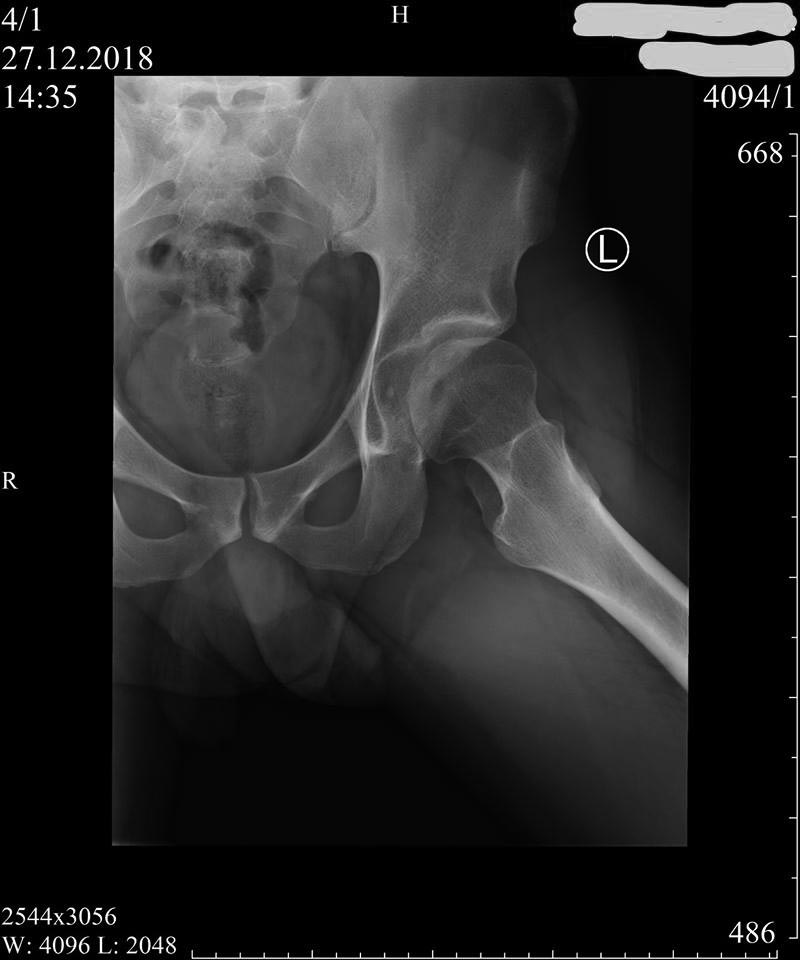

Диагностика дисплазии и импинжмента не такая сложная, на основании обычных стандартных исследовании. Прямой таз, прямой снимок каждого сустава и боковой, иногда требуется снимки в ротации: внутренняя и наружная, в аддукции и абдукции!

На представленном снимке (frog lateral) хорошо можно увидеть шейку и головку, но для данной патологии требуется false profile view! Для удобства приложил некоторые укладки: false profile и снимок с нормальными параметрами сустава (синими указаны центр край угол). Здесь имеется измененная и деформированная диспластическая форма головки, где огромный размер, выходя за пределы вертлужной впадины, создает иллюзию подвывиха. Очень узкая нагрузочная площадь и почти негативный (center-edge angle of Wiberg), потому что вертикаль (зеленая) от центра головки проходит с латеральной стороны. Контур передней стенки (синий) показывает что покрывает головку мало, а задняя стенка (красная) больших размеров доказывает что сустав развернут кпереди. Возможно за счет укладки, на рентгене слева шейка вроде короткая.